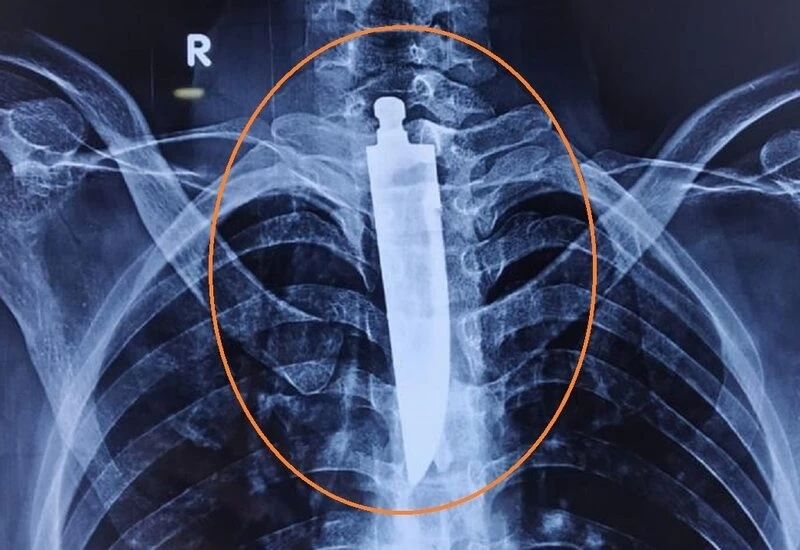

जब डॉक्टरों ने उस युवक की गर्दन का एक्स-रे किया, तो वह यह देखकर हैरान रह गया कि चाकू उसके सहयोगी नहर में फंस गया था। इसके अलावा, रोगी की एंडोस्कोपी में, यह पाया गया कि चाकू के अलावा, उसने पेन की रिफिल को भी निगल लिया। मामले की गंभीरता को देखते हुए, रोगी की सर्जरी तुरंत करने का निर्णय लिया गया।

भोपाल एम्स के निदेशक डॉ। रमन सिंह ने आजतक को बताया कि यह ऑपरेशन बहुत जटिल था क्योंकि चाकू की लंबाई 14 सेंटीमीटर थी। एलिमेंटरी कैनाल के अलावा, यह मस्तिष्क को रक्त पहुंचाने वाली नसों को भी नुकसान पहुंचा सकता है।

इसके अलावा, चाकू का तेज हिस्सा रोगी के दिल की मुख्य धमनी के बहुत करीब पहुंच गया था। सर्जरी को पूरा करने में डॉक्टरों को 4 से 5 घंटे का समय लगा। यह भी बताया गया है कि युवक पिछले दो वर्षों से मानसिक-विरोधी दवाओं का भी सेवन कर रहा है।